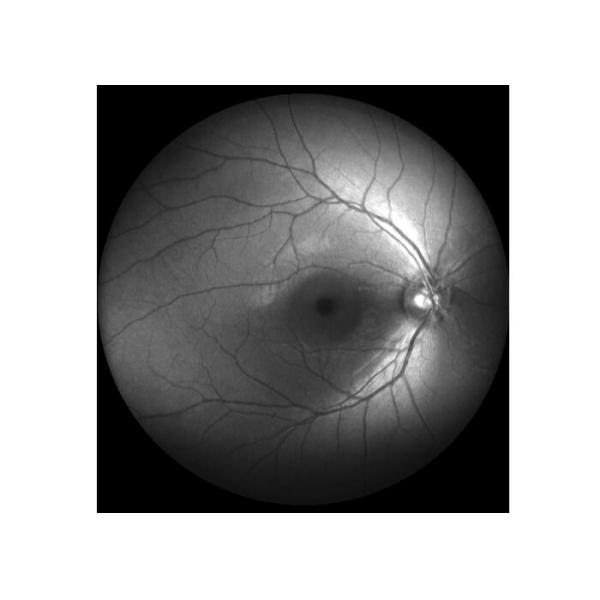

| 3 |  | Infrared(NIR) | 1) To clearly observe Macular anterior membrane and macular cystic edema 2) Comfortable, no stimulation 3) Strong penetrating |

Cases

Retina Angiograph Digital 160° Ophthalmic Equipment Images |